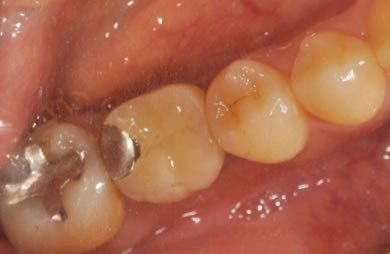

骨再生インプラント治療+セラミック治療

| 治療方針 | 左側の奥歯の部分の歯が欠如しているのでインプラント治療にて機能的・審美的回復を行いつつ、その他の虫歯の部分はセラミック歯にて治療を行う。 | ||||||||||||||||||||||||||||||||

| 治療内容 | インプラント2本(ソケットリフト)、ハイブリッドセラミック2本、オールセラミック3本(オールセラミック用の土台3本)、メタルボンドセラミック2本(メタルボンドセラミック用の土台1本) | ||||||||||||||||||||||||||||||||